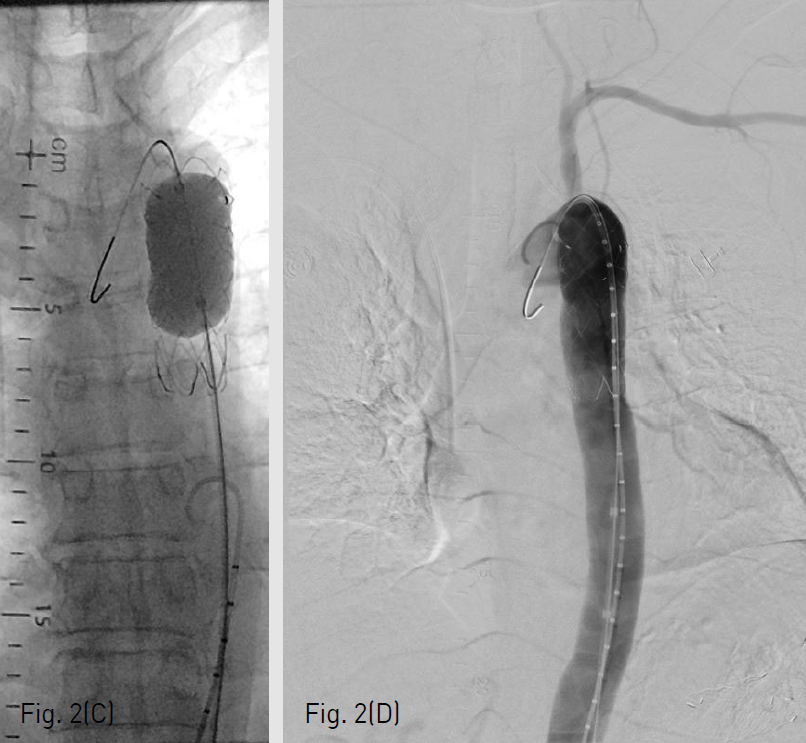

(C-D) After additional balloon inflation in the stent-graft, no contrast leakage to the aortoesophageal fistula is seen on aortogram.

우측 천자부위의 스텐트 그라프트 운반기구를 제거한 뒤 시행한 혈관조영영상에서 아직 가성동맥류로의 조영제 유출이 있음을 확인하였고 (Fig. 2B), 이에 SEAL 풍선카테터 (S&G Biotech)을 이용하여 스텐트 그라프트를 혈관벽에 밀착시켰다 (Fig. 2C). 마지막 혈관조영영상에서 스텐트 그라프트는 충분히 늘어나있고 가성대동맥류는 혈류와 완전히 격리되었음을 확인하고 시술을 종료하였다 (Fig. 2D).